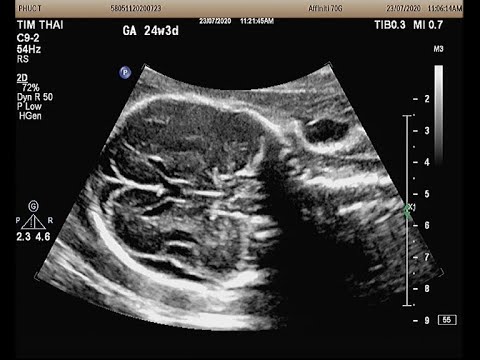

Những điều mẹ bầu cần lưu ý khi thai bị giãn não thất bên

Trẻ em bị giãn não thất thường với triệu chứng: vòng đầu tăng nhanh, đau đầu, chán ăn, hay ói mửa, thay đổi hành vi và tính cách, thay đổi thói quen, suy giảm trí tưởng, mất tập trung, mỏi mệt, thất đ